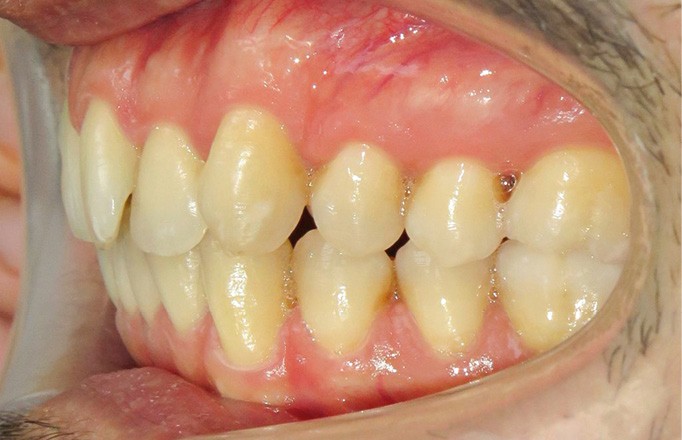

Le patient consulte initialement pour des défauts d’alignement. L’examen clinique confirme l’existence d’un encombrement antérieur bimaxillaire, mais révèle aussi la présence d’une Classe II dentaire sévère, d’une exoclusion de la 27 et de troubles parodontaux (peu ou absence de papilles inter-dentaires). Sur le plan squelettique, le patient est relativement équilibré avec un profil harmonieux.

Diagnostic (fig. 1a-i)